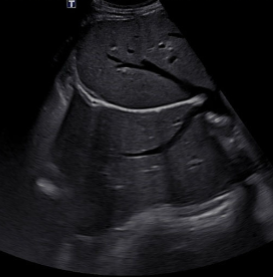

Propagation Speed Error

Caused by a structure of lower or higher velocity than 1540 m/s (what the machine assumes)

Appears as:

Vertical displacement behind area of non-1540 m/s

Faster = shallower

Slower = deeper

Distortion of shape of the object

Cannot be eliminated

The image shows a hemangioma that causes a slower velocity and therefore makes a part of the diaphragm appear deeper than it really is

1540 m/s, Vertical, 1540, shallower, deeper, shape, Cannot